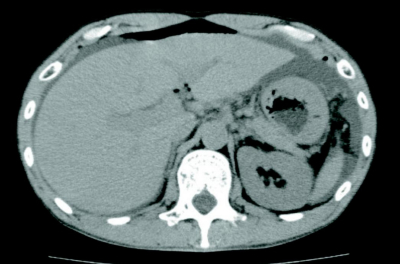

血液所見:赤血球 483万、Hb 15.7 g/dL、Ht 47%、白血球 14,700、血小板 30万。血液生化学所見:総蛋白 7.3 g/dL、アルブミン 4.2 g/dL、総ビリルビン 0.9 mg/dL、AST 20 U/L、ALT 15 U/L、LD 170 U/L(基準120〜245)、ALP 265 U/L(基準115〜359)、γ-GT 66 U/L(基準8〜50)、アミラーゼ 52 U/L(基準37〜160)、CK 85U/L(基準30〜140)、尿素窒素 17 mg/dL、クレアチニン1.0 mg/dL、血糖 103 mg/dL、Na 146 mEq/L、K 3.8 mEq/L、Cl 106 mEq/L。CRP 2.2 mg/dL。腹部単純CTを別に示す。

まずは手術を実施せず、保存的治療を行うこととした。対応として適切なのはどれか。3つ選べ。